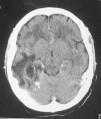

Ingresó en un hospital comarcal por presentar cuadro de fiebre, cefalea, náuseas y vómitos de 48 horas de evolución. Se realizó tomografía axial computarizada (TAC) craneal sin contraste (fig. 1), apreciándose lesión temporoparietal derecha de 2,8 x 2,6 cm compatible con absceso cerebral.

Figura 1. Lesión hipodensa temporoparietal derecha.